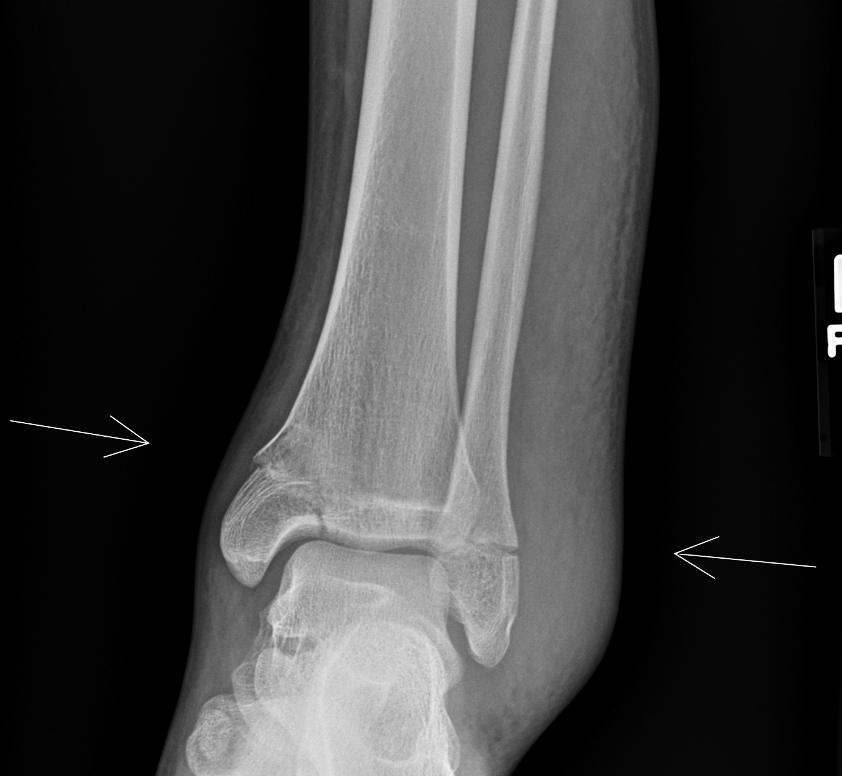

Info Images Findings Impression Reco/Acuity Case Images View Images / Launch Visage Case Notes History 2-month-old presents with decreased right arm movement, increased fussiness, and increased sleepiness for 2 days. Suspected non-accidental trauma. Exam Skeletal survey Prior Study none Dicom View Reference Material

Section 1 Submit Findings CB1550 Findings Skeletal Survey - Technique Check Skull AP/Lat Yes No Cervical and Thoracolumbar spine Yes No Chest X-Ray Yes No Ribs – Left/Right Oblique Yes No Abdominal X-Ray Yes No Pelvis with both hips Yes No Bilateral Humerus, Forearm, Hand Yes No Bilateral Femur, Tibia/fibula, feet Yes No Any additional lateral views of the extremities Yes No The exam is over or under penetrated. Yes No The exam may or may not be limited by overlying structures or soft tissues, body habitus, patient positioning, support devices, or motion. Yes No The area of concern is indicated by the patient, technologist, or care provider. Yes No The area of concern is included on the exam. Yes No Soft Tissues There is soft tissue swelling, indistinctness of fat/muscle planes, gas, or laceration in the area of clinical concern. Yes No There is an effusion, fat pad displacement, or fat fluid level. Yes No There is a radiodense or lucent foreign body. Yes No There are other densities, calcifications, post-surgical changes, or support devices in the soft tissues. Yes No Any support lines/tubes. Yes No Bone There is a break or interruption of the continuity of the cortical or cancellous bone. Yes No There is overriding of the trabeculae with apparent sclerosis. Yes No There is displacement of a fracture fragment. Yes No There is bowing of the bone in addition to the fracture at the apex of the bowed bone concerning for the greenstick. Yes No There is a spiral fracture of the leg concerning for toddler’s fracture. Yes No There is abnormal angulation or bulging of the cortical surface relative to the normal cortex which could be from a buckle or torus fracture. Yes No There is a displaced fragment which may be from avulsion by a tendon, ligament, or joint capsule or from a comminuted or other fracture. Yes No The stress trabeculae or other trabeculae of the cancellous bone are interrupted or otherwise abnormal. Yes No There is subperiosteal or endosteal reaction which could indicate a healing or subacute fracture or other abnormality. Yes No There is hard/soft callus formation. Yes No There is remodeling of the bone. Yes No There is a corner fracture or metaphyseal lesion that could be from nonaccidental trauma. Yes No There are multiple fractures of different ages. Yes No There are vertebral body/spinous process fractures. Yes No There are rib fractures. Location - posterior or lateral. Yes No There is scapular/sternal fracture. Yes No There are fractures of the digits. Yes No There are wormian bones. Yes No There are intrasutural bones. Yes No There is metaphyseal abnormality (lucencies, increased density, erosion) which may be from something other than injury such as stress, metabolic disease (e.g. rickets with loss or distortion of the zone of the provisional calcification), neoplasm (e.g. leukemia), heavy metals, inflammation, or infection. Yes No There are metaphyseal spurs. Yes No There are bony deformities involving multiple bones. Yes No The bones are gracile. Yes No There are non-healing fractures. Yes No There is/are focal or multifocal lytic/lucent, blastic/sclerotic or mixed density lesion(s) or other abnormality. Yes No Overall bone density is increased or decreased with or without thinning or thickening of the cortical or cancellous bone. Yes No Growth plates, ossification centers, apophyses The growth plate(s) is/are abnormal. Yes No There is widening of the physis from a fracture with or without displacement of the epiphysis (Salter-Harris I). Yes No There is a fracture through the physis which then extends into the metaphysis with or without angulation or displacement (S-H II). Yes No There is a fracture through the physis which then extends into the epiphysis and is intra-articular, with or without angulation or displacement (S-H III). Yes No There is a fracture through the metaphysis, physis, and epiphysis which extends into the joint space with or without angulation or displacement (S-H IV). Yes No There is narrowing of the physis from a compression fracture (S-H V). Yes No The apophysis, epicondyle, secondary ossification center, or accessory ossicle is displaced or otherwise abnormal. Yes No The ossification centers are underdeveloped. Yes No Joints and alignment There is an effusion, fat pad displacement, or fat fluid level. Yes No The epiphysis or subchondral bone is fractured, interrupted, flattened, compressed, impacted, displaced, or otherwise abnormal. Yes No There is an intra-articular loose body or chondrocalcinosis. Yes No The joint is widened, narrowed, dislocated, malaligned, or incongruent. Yes No There is pseudoarthrosis. Yes No Other findings There are developmental changes or other anatomic variants or other existing conditions that may or may not be contributing to symptoms which can or should be further evaluated non-emergently or are otherwise incidental. Yes No The remainder of the exam is abnormal for age. Yes No The lungs show focal airspace opacity. Yes No There is pneumothorax. Yes No There is organomegaly. Yes No There is intra-abdominal calcification. Yes No There is displacement of the bowel loops. Yes No There is free intraperitoneal air. Yes No The bowel loops are dilated/obstructed. Yes No There is paraspinal soft tissue abnormality. Yes No